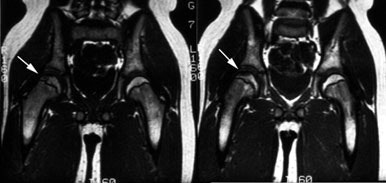

Legg-Calve-Perthes: The child shown below was being evaluated for right hip pain. The bone scan demonstrated a focal area of photopenia in the lateral aspect of the right femoral head (black arrow) consistent with avascular necrosis. (Click the planar images to view selected SPECT images). T1-weighted MR images from the same patient demonstrate signal loss in the right femoral head epiphysis. A focal area of signal void can be seen in the lateral aspect of the epiphysis. (Click MR image to enlarge) |